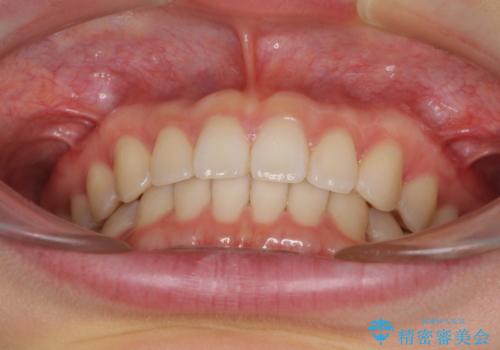

インビザラインによるすきっ歯の改善

下顎の歯列が強く上顎に咬みこむことで隙間ができてしまうため、マウスピースの保定装置では後戻りのリスクが高くなってしまいます。

そのため、上下ともに前歯の裏側を細いワイヤーで固定し、その上から保定装置のマウスピースを使用していただくこととしました。